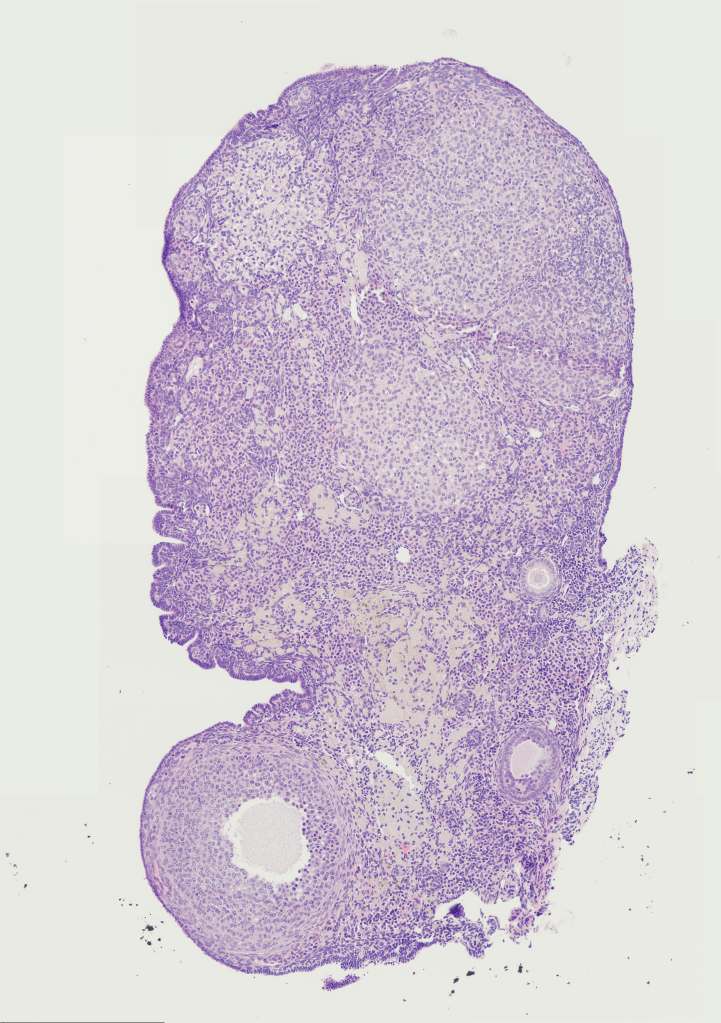

Imaged by Milan Singh

Milan is a second year PhD student studying ovarian ageing. She is interested in investigating the stiffness and material properties of the organ across a wide range of ages using biophysics, proteomics and biochemistry. Previously, she completed her undergraduate in Chemistry with Biomedicine and her Master’s year in single-molecule Biophysics.